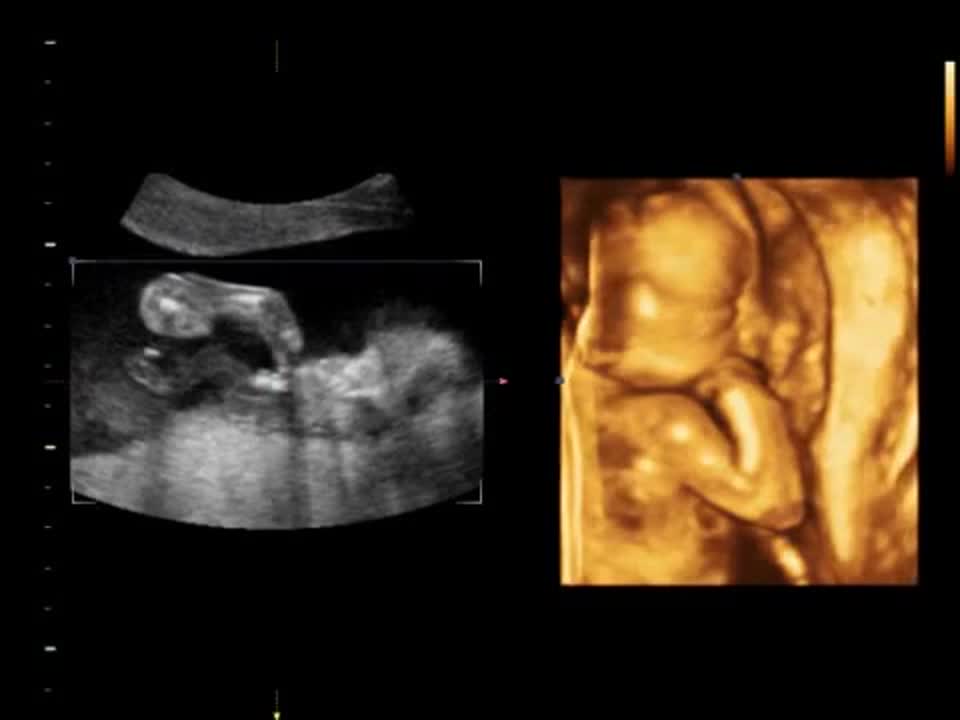

Скрининг 19 Недель Фото

Скрининг 19 Недель Фото 120 фото

13 14 Недель Беременности Фото